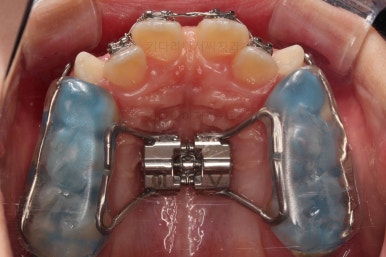

입 안에는 이런 장치가 들어가요.

착탈식은 아니고 부착형입니다.

앞니를 일부러 붕 띄워주며 위턱의 가로폭을 확장시켜주는 악궁확장장치도 부착이 되었어요.

어떻게 식사를 하냐며 걱정하시는 보호자분들이 계시지만 씹는 면을 편평하게 아랫니와 맞춰주었기 때문에 기존의 부정교합인 상태보다 오히려 식사가 잘 될 수 있으니 염려 안하셔도 됩니다.